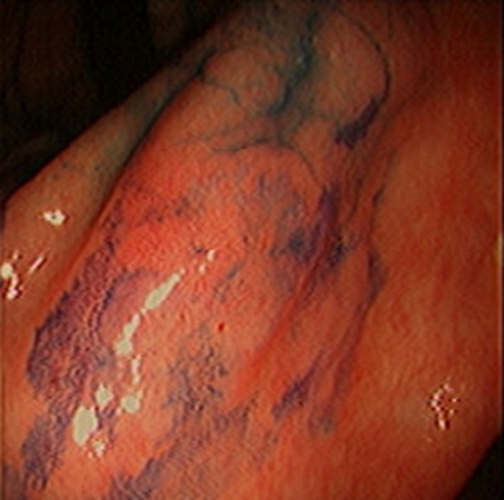

急性胃炎圖片

急性胃炎陽性表現

急性胃炎陽性的表現

急性胃炎